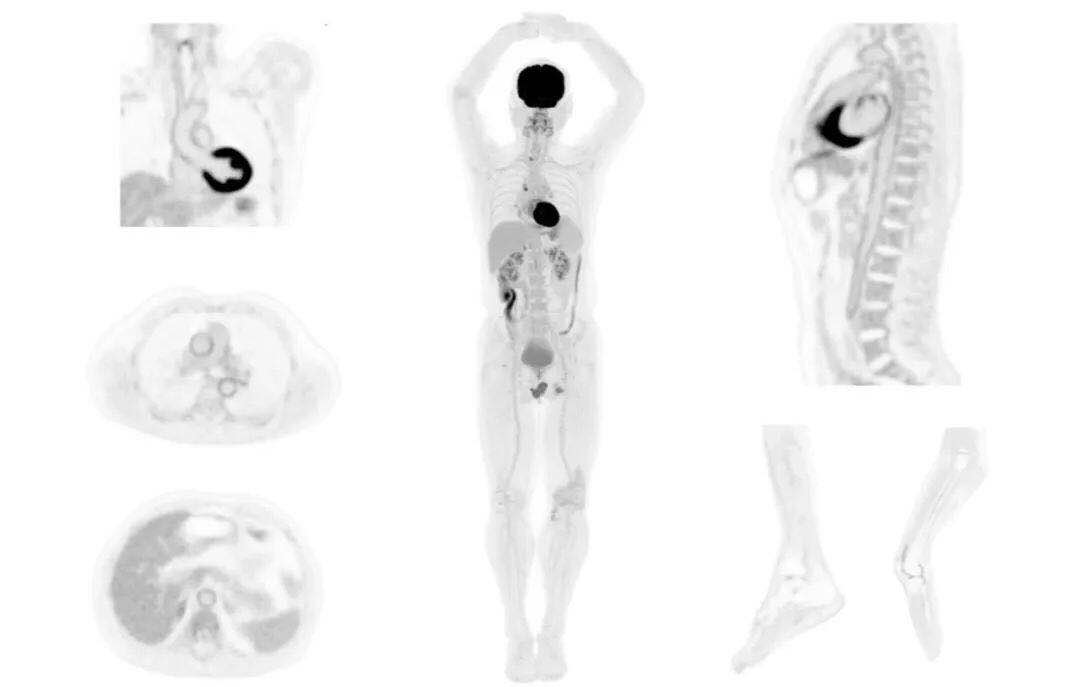

直腸癌

男,45歲,直腸癌術(shù)后9個月,發(fā)現(xiàn)肺占位

臨床診斷:直腸區(qū)術(shù)后改變,復發(fā)伴骶骨受累,雙肺多發(fā)轉(zhuǎn)移